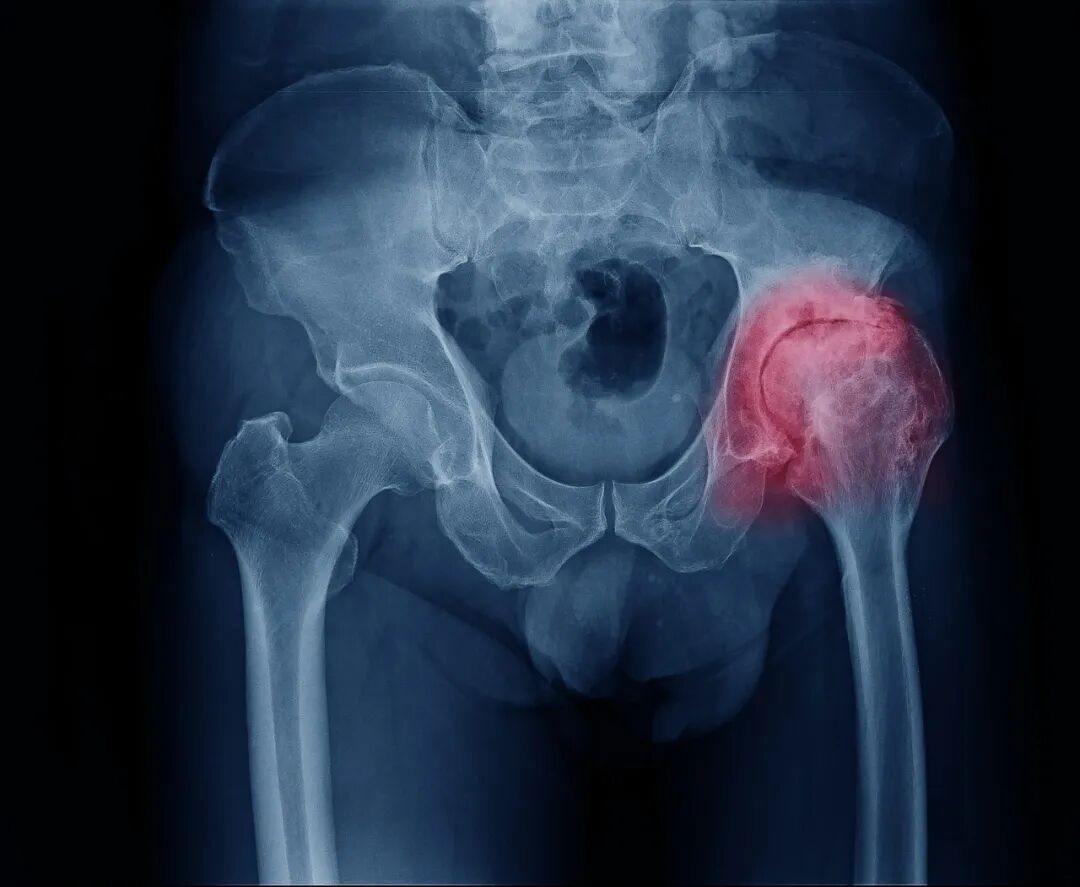

股骨头坏死(ONFH)又称缺血性股骨头坏死,是骨科中常见的难治性疾病,主要病因是股骨头血液供应遭到破坏,导致骨髓成分减少与骨细胞死亡,最终股骨头坏死塌陷,引起髋部疼痛,降低患者的生活质量。

造成骨坏死的原因不消除,修复不完善,损伤修复的过程继续,导致股骨头结构改变、股骨头塌陷、变形,关节炎症,功能障碍。股骨头坏死会引起病痛,关节活动和负重行走功能障碍。